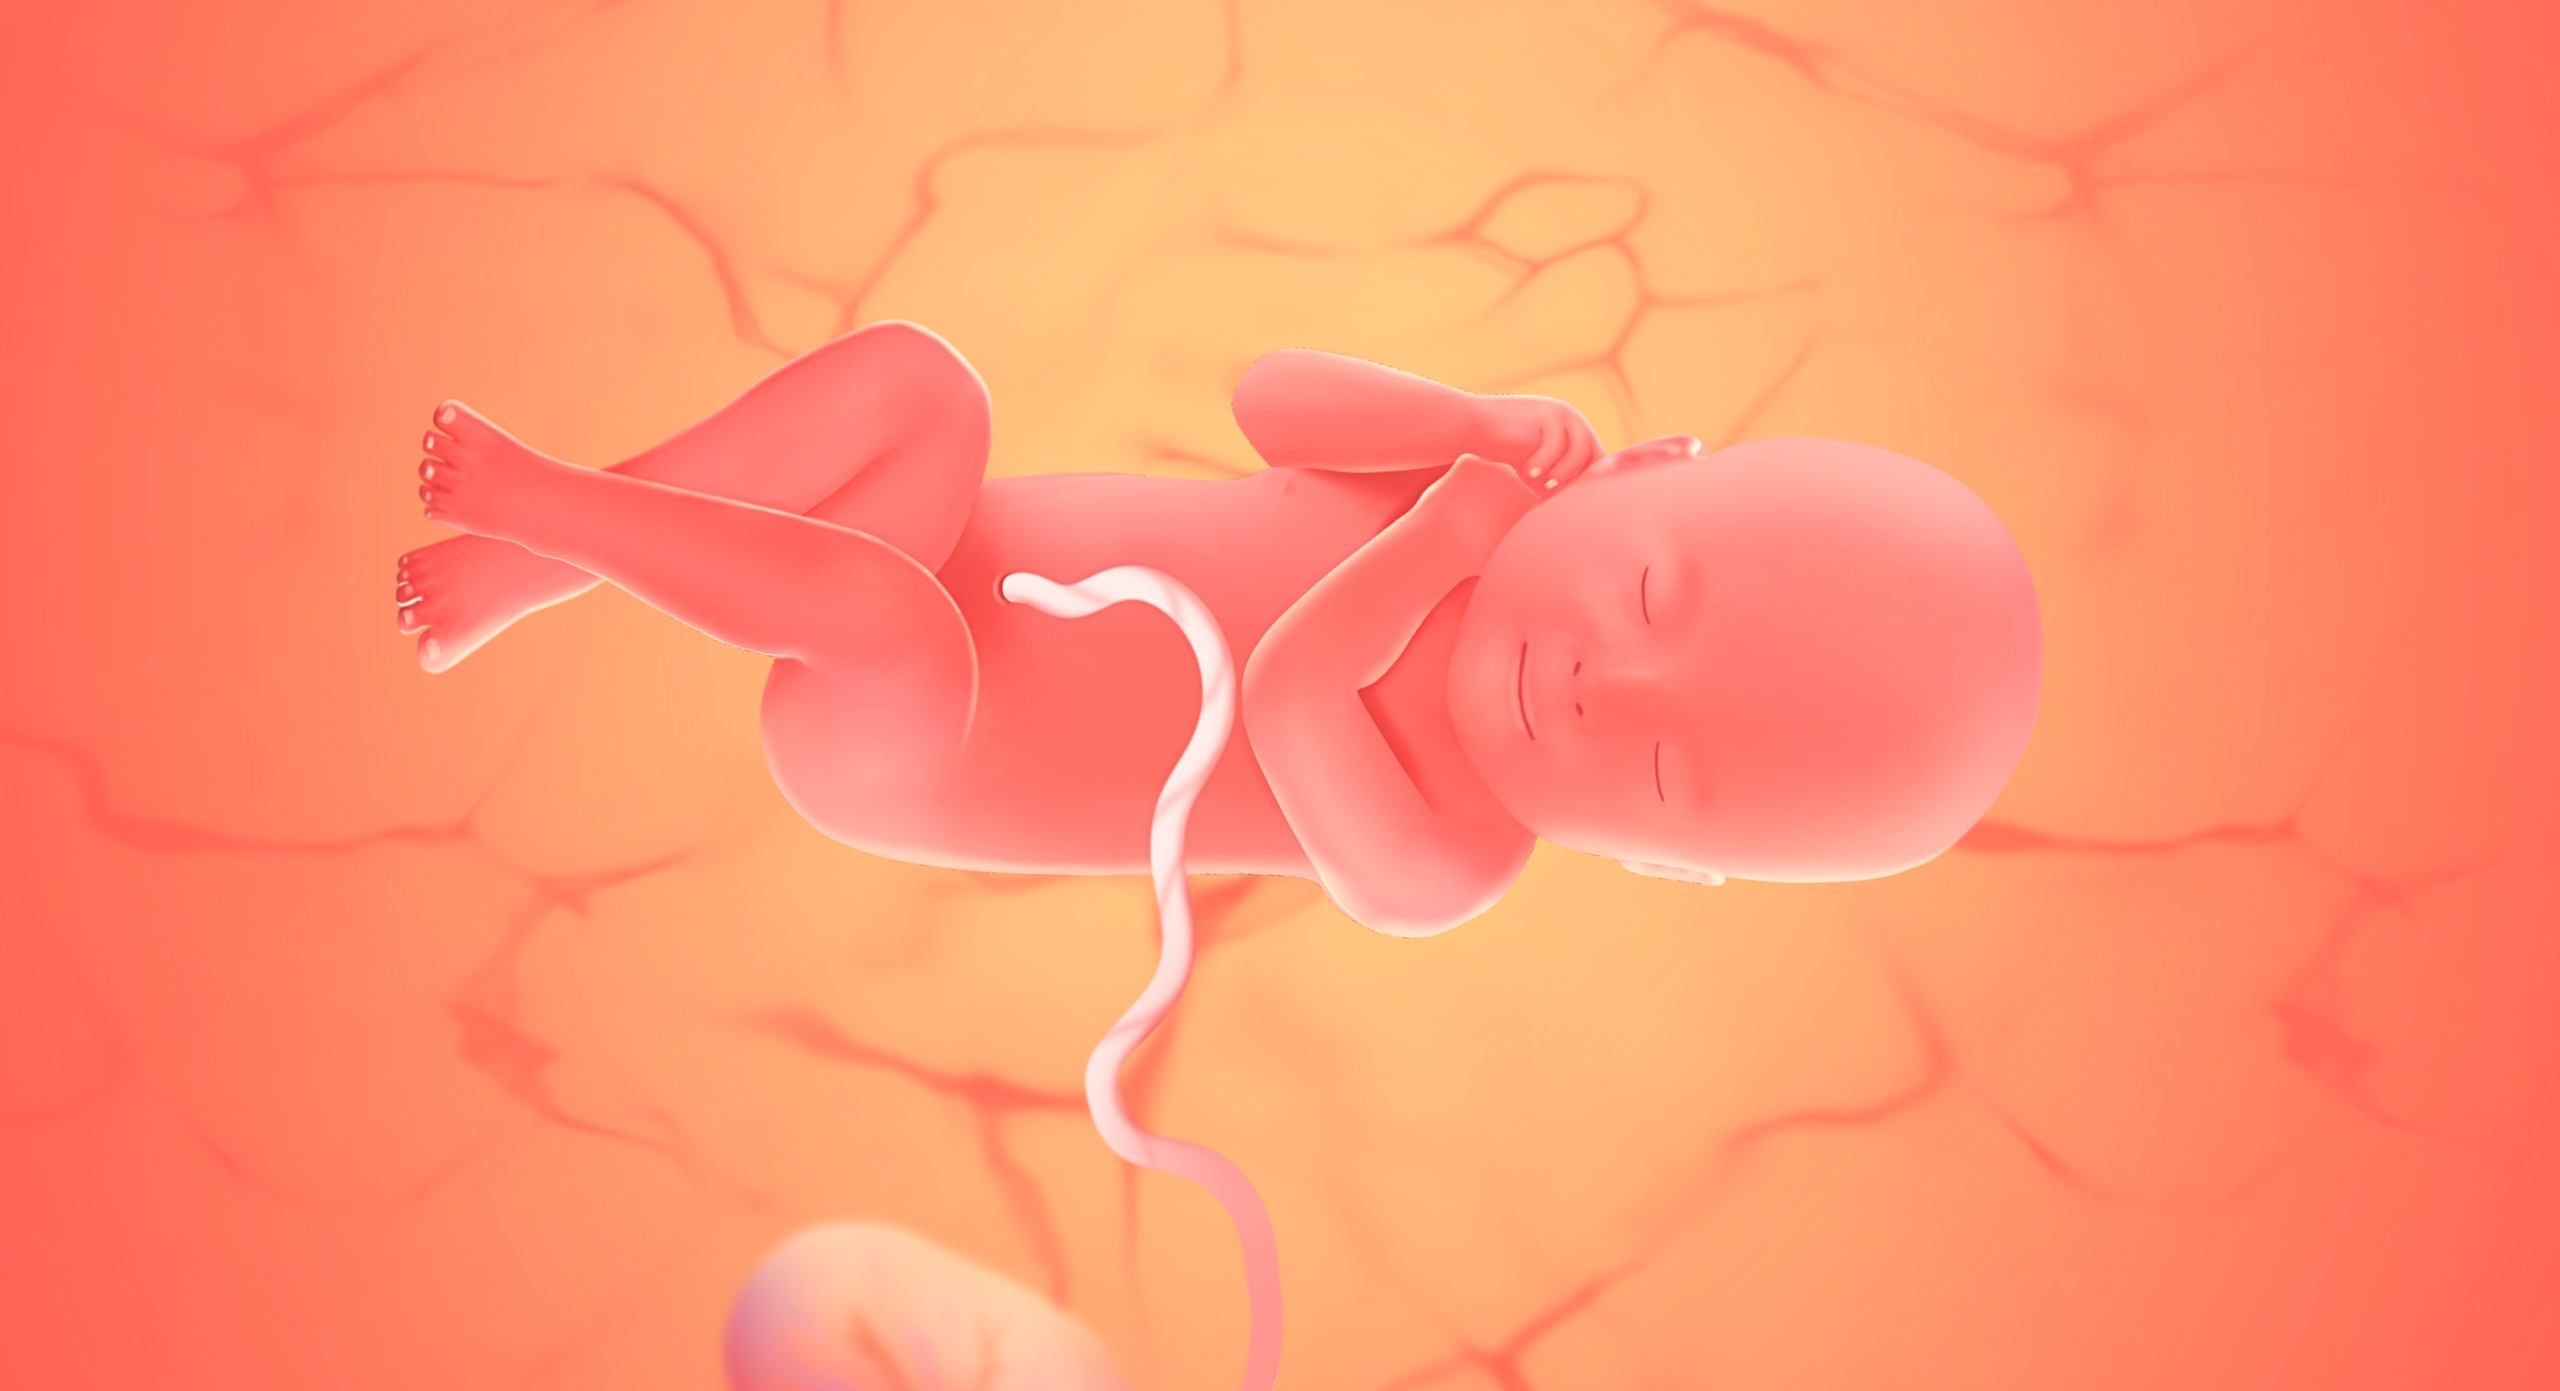

Gravid vecka 41 (40+0 - 40+6)